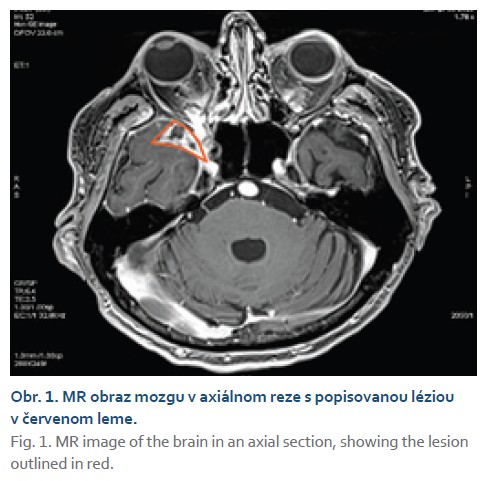

In March 2023, the patient was referred to the Department of Hepatology, Gastroenterology, and Transplantation (HEGITO) at the F. D. Roosevelt University Hospital in Banská Bystrica for further evaluation. The patient continued to experience headaches of a rather episodic nature, particularly at night, and a few days before hospitalization, the patient again experienced loss of vision in the right eye. At the onset of hospitalization, we performed an emergency contrast-enhanced CT scan of the brain, which revealed a enhancing lesion measuring 20 × 13 mm located on the right greater sphenoid wing, extending into the orbit and into the right optic canal, where it partially involved the dorsal quarter of the optic nerve. Subsequently, a follow-up brain MRI confirmed the

aforementioned lesion with involvement of the optic nerve and, to a lesser extent, the medial rectus muscle of the orbit. Based on imaging findings, radiologists leaned toward a diagnosis of a suspected tumor likely meningioma; the possibility of an abscess was less likely (Figs. 1, 2).